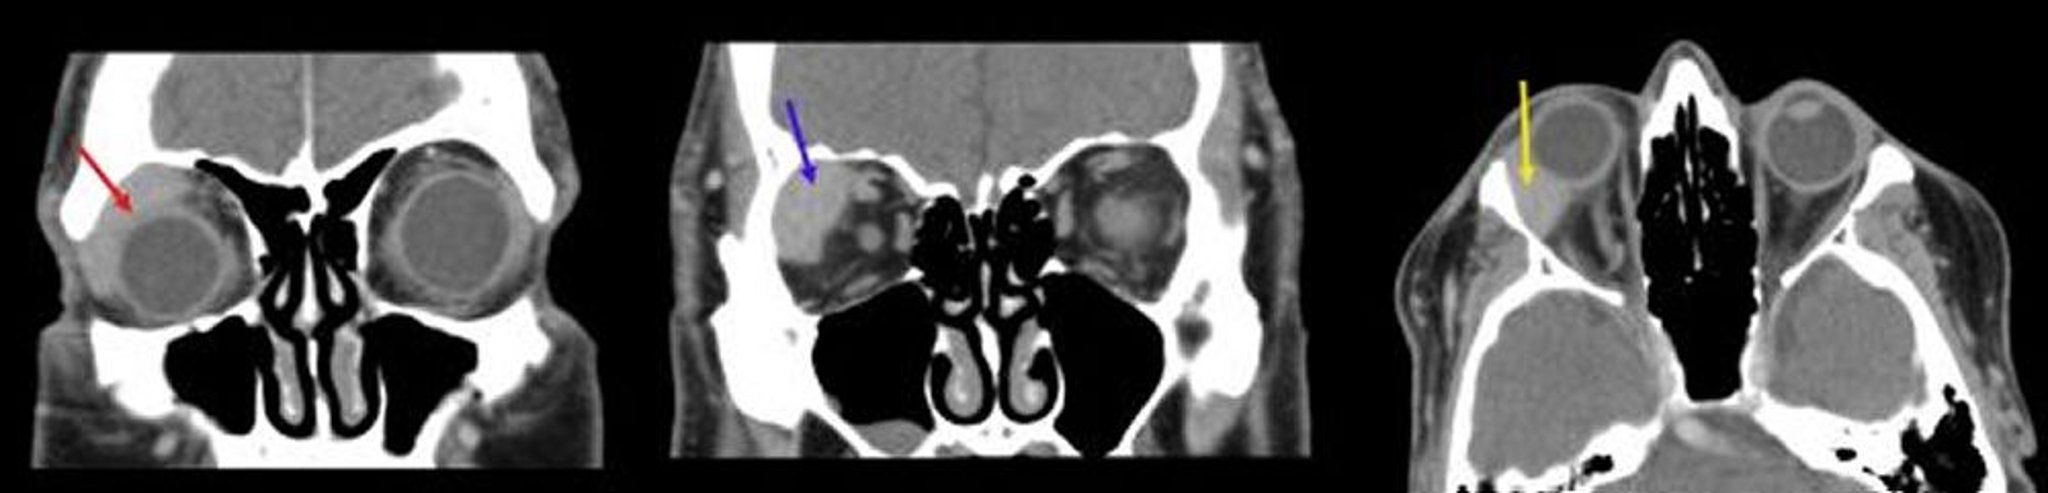

Lymphome orbitaire

Dans cette image, la première TDM coronale (à gauche) montre une masse homogène qui se conforme avec le globe (flèche rouge). La deuxième TDM coronale (au centre) montre une masse bien délimitée dans la fosse de la glande lacrymale droite (flèche bleue). La TDM axiale (à droite) montre une masse lacrymale homogène qui se conforme avec le globe droit (flèche jaune).

Images courtesy of James Garrity, MD.